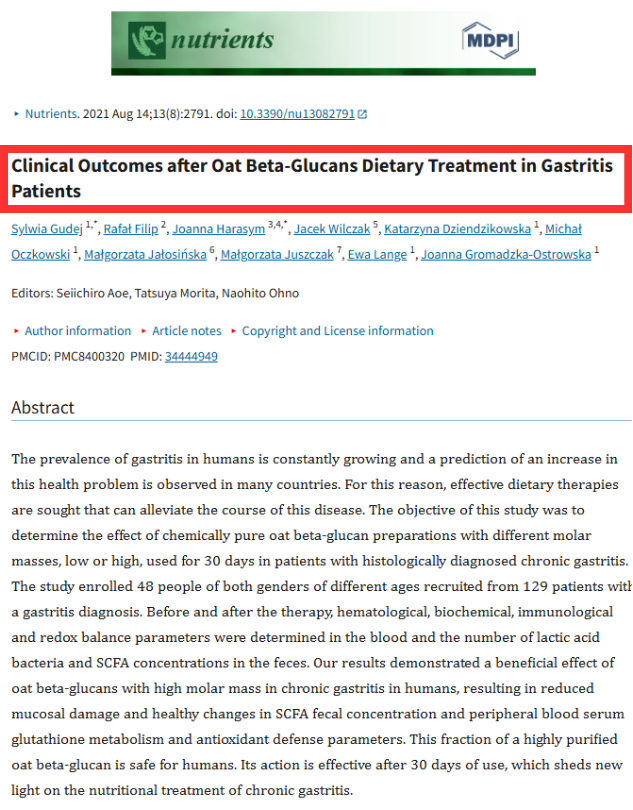

Kajian klinikal kesan Beta Glucan kepada pesakit gastrik